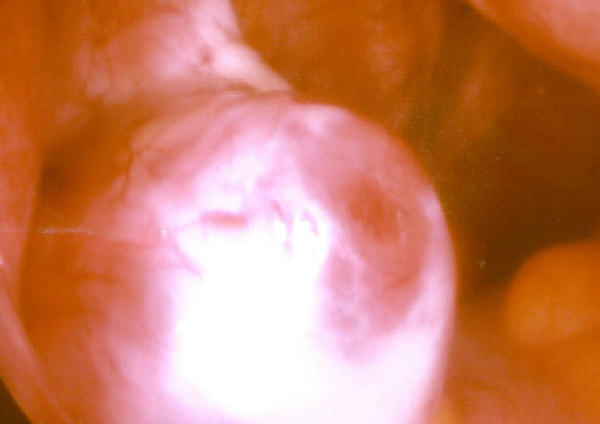

Naderende ovulasie

Impending ovulation